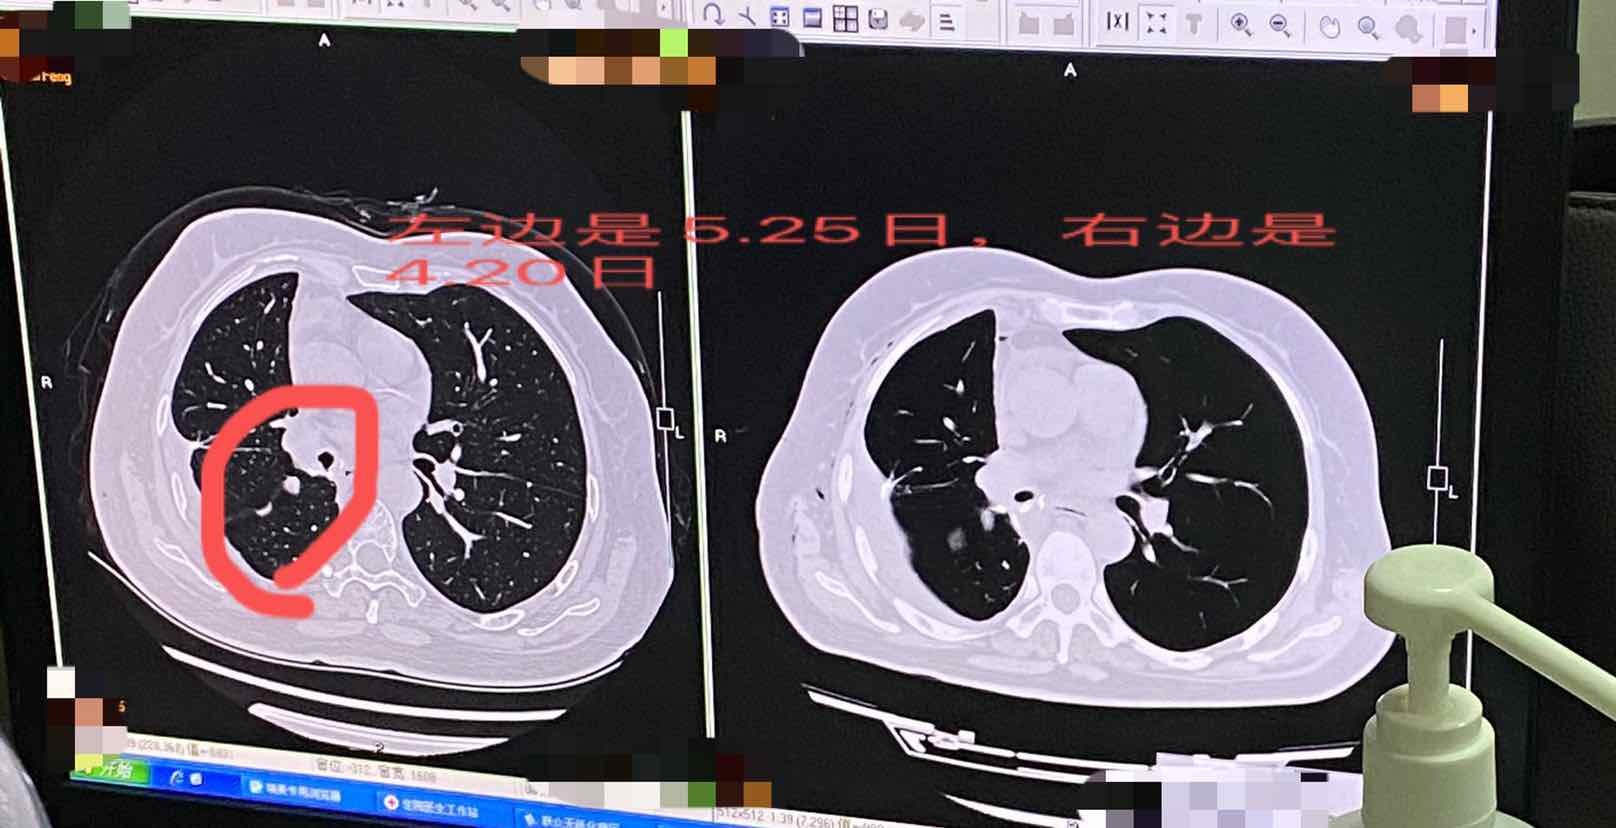

她55岁,肺腺癌一期,于今年3.25日体检,报告单显示双肺上叶有磨玻璃结节,大小约为0.6*0.5cm,4月7日做微创胸腔镜手术切除了右肺下叶恶性结节,2.5*2.1cm,右肺上叶通过穿刺活检定位,切除了3mm的微小结节,病理呈良性。于4月20日做了胸部平扫,医生说没啥事。之后于5.25日又去做检查,报告显示双肺上叶散在磨玻璃小结节,较大的直径约为6.5mm,【这和3.25日体检报告特别相似】去找医生看片子,却说在右肺上叶和中叶叶间裂有两个结节,一个在边缘处,一个在中间。说在中间那个位置的结节不太好。但我一直觉得3.25日和4.20日的报告都显示在双肺上叶结节,大小都是差不多的,觉得应该一直就存在这个结节。3.31日增强版ct无显示双肺上叶有结节。可是医生看增强版片子确实没有,但5.25日的片子上有描述的位置在叶间裂处,主治医师说是新长出来的,但是两个月能长6.5mm的结节吗?是不是太快了?我充满了怀疑…也有个医生说,可能是手术中不小心扩散了……目前没有谁能肯定…